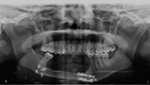

40 year-old man with history of facial trauma, status post mandibular reconstruction. A mandibular radiograph (A) demonstrates mandibular reconstruction on the right side with loss of bone and teeth. Tc-99m MDP (B) bone scan demonstrates uptake within the body of mandible on the left side which is due to altered stress from chewing. |

| 40 year-old man with history of facial trauma, status post mandibular reconstruction. A mandibular radiograph (A) demonstrates mandibular reconstruction on the right side with loss of bone and teeth. Tc-99m MDP (B) bone scan demonstrates uptake within the body of mandible on the left side which is due to altered stress from chewing. |